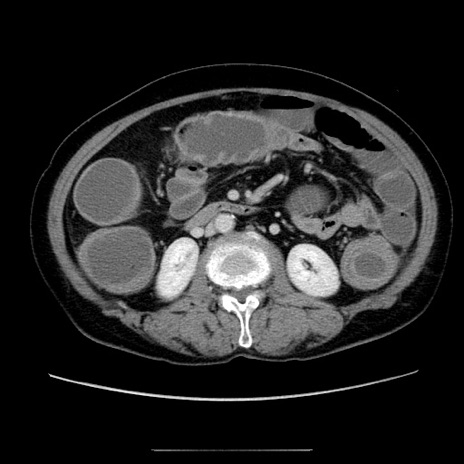

症例5(横断像)

【症例】70歳代女性

【主訴】お腹が張る

【現病歴】1週間くらい前から腹部膨満の自覚あり。昨日夜から増悪したため、本日救急外来受診。

【身体所見】意識清明、BT 36.5℃、BP 165/106mmHg、HR 80bpm、SpO2 98%、腹部:膨満、軟、自発痛・圧痛なし、触診にて不快感あり、腸蠕動音:減弱

【データ】WBC 12600、CRP 1.04